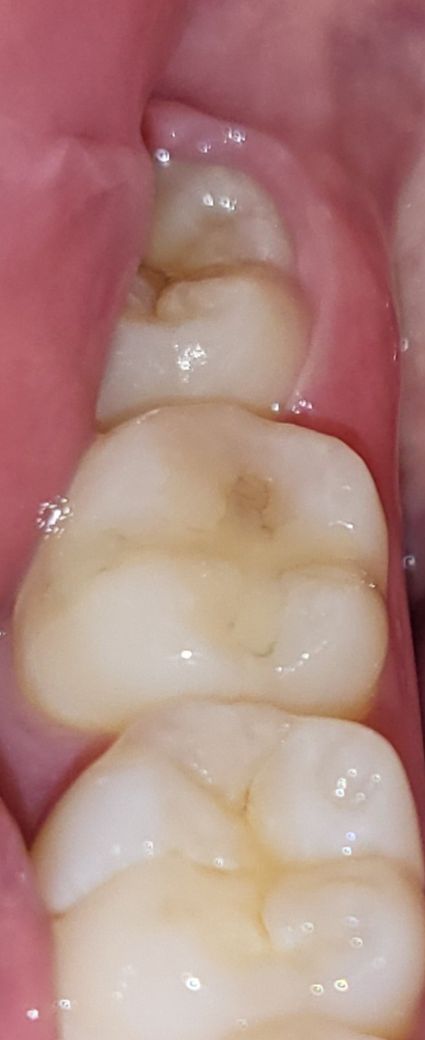

레진 1년 후 2차충치인가요 ? 치료했던 치과 재방문

통증이 와서 확인해봤는데 살짝 거뭇거뭇한 색이 돌더라고요

안쪽이 썩은걸까요 ?

레진 치료하고 1년정도 지났는데 이렇게 빨리 재발 될 수도 있나요

치료받으신 치아는 #47 (협면과 교합면, BO 레진수복 치료)으로 보여지며 레진 수복물 상방의 검은 건 변색으로 인해 떼 낀 것입니다.

추가적으로 사랑니에 대한 평가도 필요해 보입니다. 사랑니와 그 부위 잇몸에서 비롯된 통증일 가능성도 있습니다. 현재 사진상으로 사랑니 부위 잇몸이 조금 부어 있고 씹는면 충치가 있습니다. 이런 경우 사랑니 발치하면 증상은 완화됩니다.

저부위는 충치라기 보다는 주변부가 변색이 됫을가능성이 높습니다. 통증이 잇다면 사랑니쪽이 관리가 안되서 그럴가능성이 높습니다.